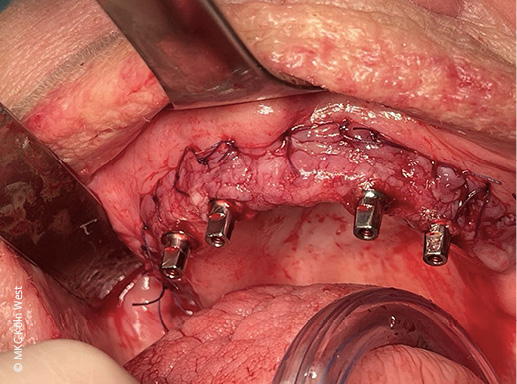

Direkt im Anschluss an die Implantation wurde durch die prothetische Überweiserin eine provisorische Brücke auf dem Implantatgerüst verschraubt, sodass die Patientin bereits beim Erwachen aus der Narkose mit festsitzenden Zähnen versorgt war.

Nach erfolgter Alveolarkammglättung wurde jeweils rechts und links ein Implantatsegment passgenau aufgelegt und mit dem 1,5 mm MaxDrive-Schraubensystem fest am Knochen fixiert. Sechs transgingivale Pfeiler wurden durch entsprechende Stichinzisionen ausgeleitet und das Gerüst analog zu Fall 1 vestibulär mit verschobenem Bichat-Fettgewebe abgedeckt.

Intraoperativ konnte auf den sechs Pfeilern eine provisorische Interimsbrücke verschraubt werden, die eine sofortige provisorische Versorgung gewährleistete. Nach komplikationsfreier Wundheilung erhielt die Patientin acht Wochen postoperativ die definitive festsitzende Brückenversorgung im Oberkiefer.